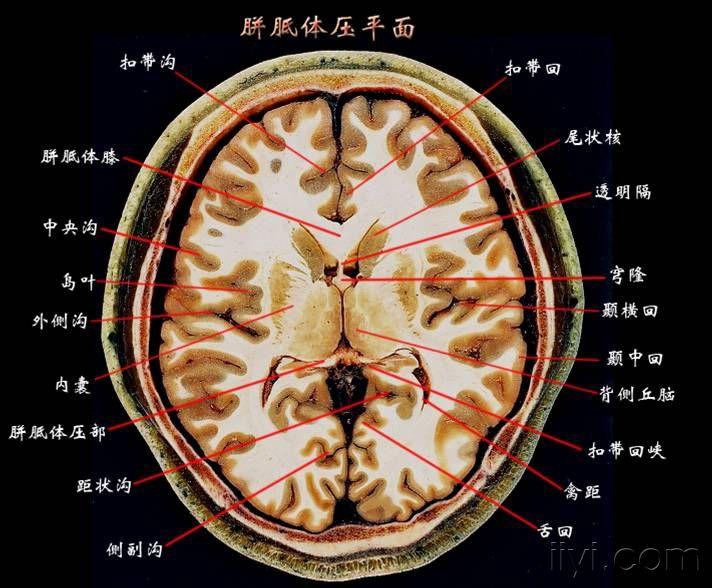

这个高清颅脑断层解剖图谱实在太棒了!【磁共振 大体标本】

颅脑断层解剖轴位

颅脑断层解剖